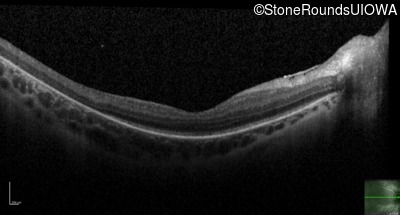

Age at visit: 16 years

This 16 year old female has had poor visual acuity and poor vision in dim light for most of her life. She has normal hearing and no cognitive difficulties.

SECORD RPE65 IVS1+5 G>A Arg124Stop CGA>TGA AR